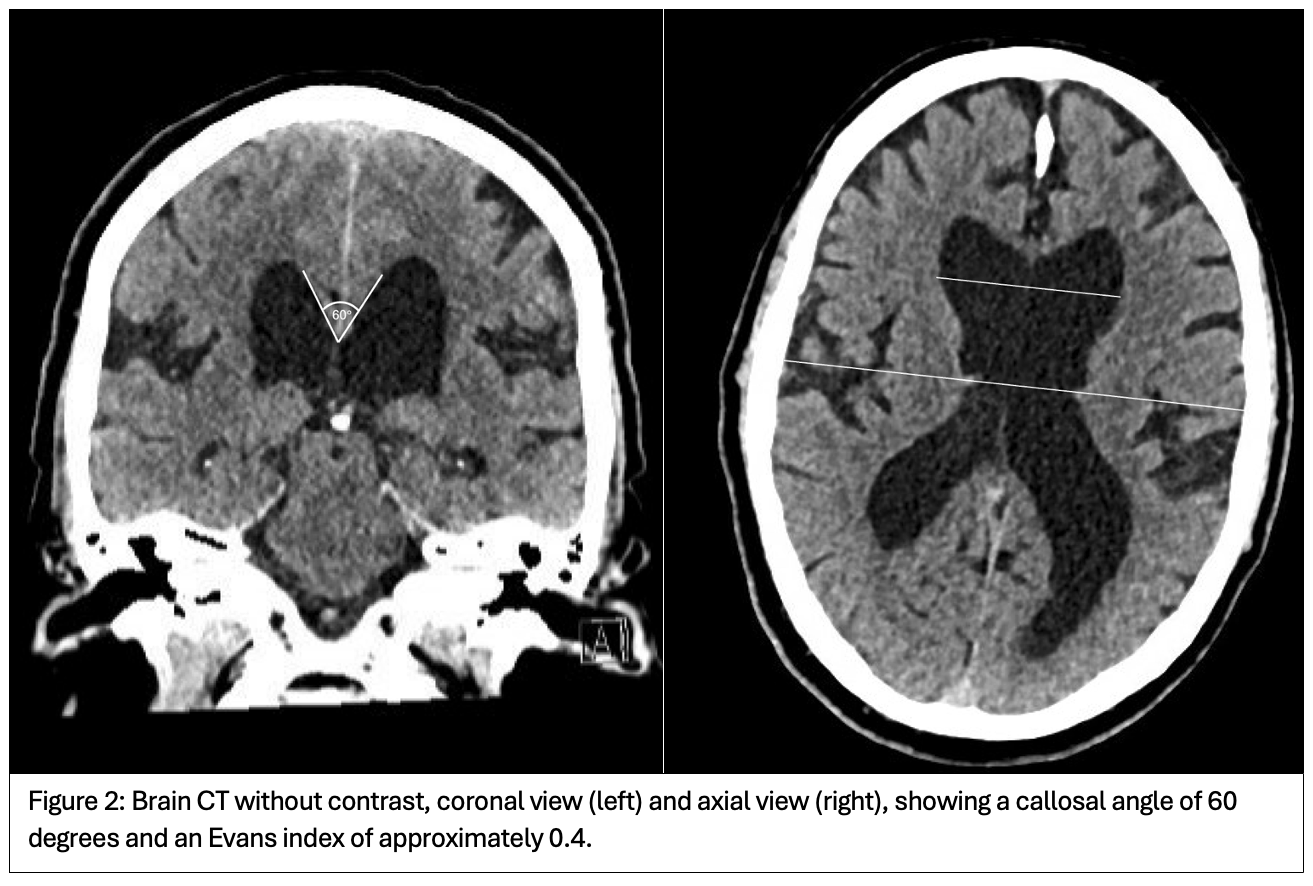

Brain MRI (Figure 1) and CT (Figure 2) showed findings consistent with NPH and a 0.6 mm colloid cyst at the foramen of Monro. The patient was treated with carbidopa/levodopa 25/100 mg, one tablet four times daily, but experienced no clinical improvement. He will be scheduled for a large-volume lumbar puncture to assess potential responsiveness to CSF drainage as a treatment for NPH.

Conclusion: This case emphasizes the difficulty of distinguishing atypical parkinsonism from secondary causes such as NPH. Despite gait impairment, oculomotor dysfunction, and levodopa unresponsiveness, the presence of NPH on MRI and a normal midbrain-to-pons ratio raise concerns for an alternative or overlapping etiology. Further evaluation via CSF drainage will help clarify the role of NPH in his symptoms and guide management.

Figure 2